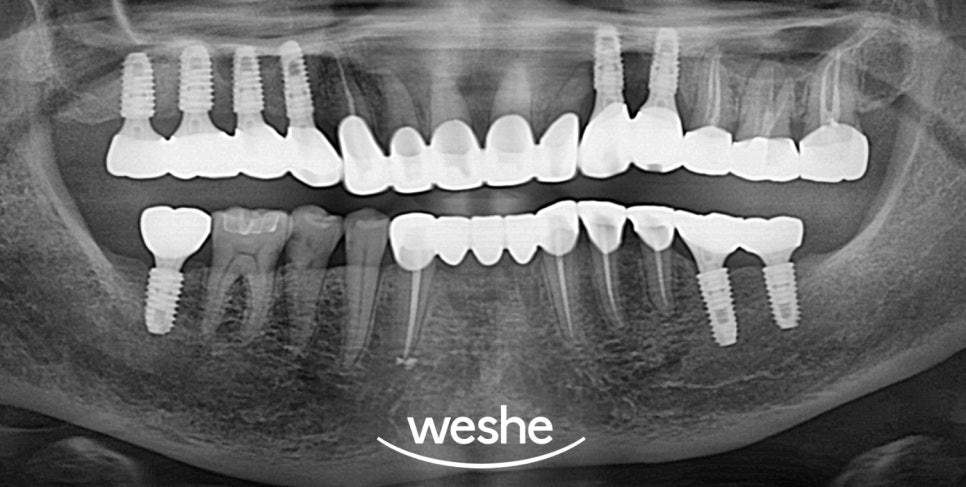

픽스처 식립을 진료 방법으로 선정한다면

3D-CT를 이용하여

구강 내 정보를 분석한 뒤

먼저 구강 내 정보를 취득하여

당일 임시 치아를

사용할 수 있도록 제작합니다.

치조골과 픽스처가

충분히 유착된 것을 확인한 뒤

최종 보철을 제작합니다.

※ 최종 보철물 완성 시기는

환자의 구강 상태, 진료 일정 및 기공실 운영 방식 등에

따라 상이할 수 있습니다.

제작된 보철을 구강 내 체결할 때는

원하는 색조로 제작이 되었는지,

위아래 맞물림은 편한지 등을

확인하는 것이 좋습니다.

치료 기간 : 2024.12.05~2025.06.12